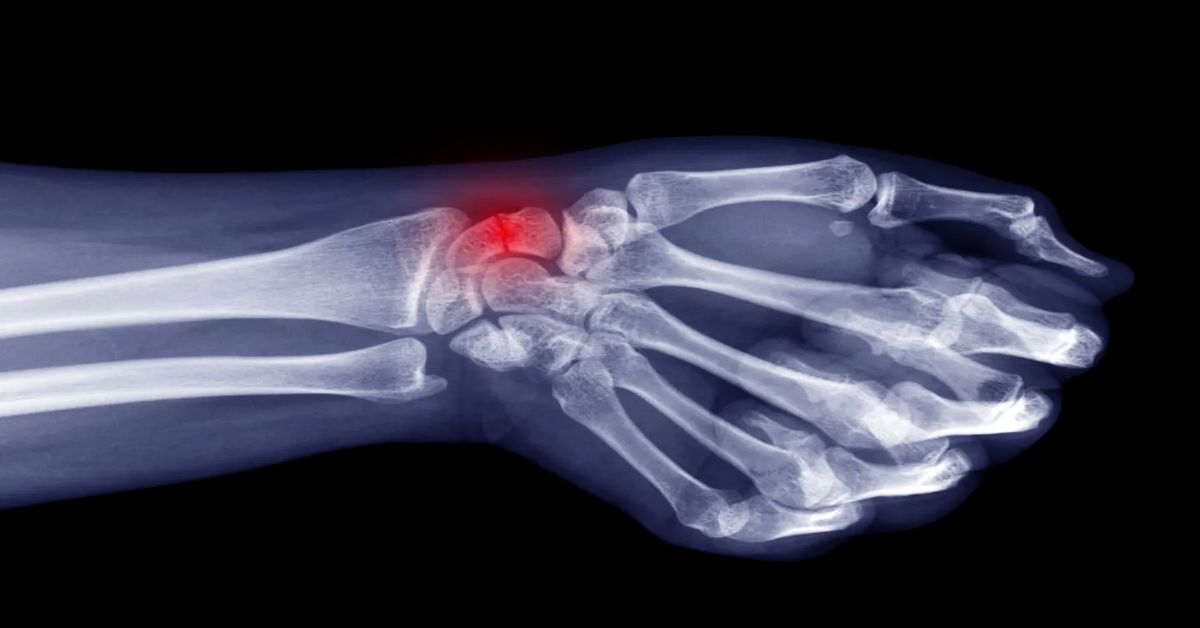

Genellikle ayak, tibia (kaval kemiği) ve koşucularda diz çevresindeki kemiklerde görülür. Ani travmalardan kaynaklanan kırıklardan farklıdır; zamanla ve sürekli yüklenmeyle gelişir. Stres kırığı, kemikte tekrarlayan baskı ve zorlamalar sonucu oluşan küçük çatlaklardır.

Yoğun spor yapanlar, uzun süre koşanlar ve dansçılar, stres kırığı riski altındadır. Belirtiler arasında sürekli ağrı, hassasiyet ve etkilenen bölgede şişlik yer alır. Aktivite sırasında ağrı artarken, dinlenme ile azalır. Ayak, tibia ve diz çevresinde küçük morluklar veya hafif şişlik görülebilir. Bu kırık türü genellikle ani travmalardan kaynaklanmaz; tekrar eden baskılar sonucu gelişir.

Tedavi edilmezse, küçük çatlaklar daha büyük kırıklara dönüşebilir. Bu durum hem iyileşme süresini uzatır hem de günlük yaşamı etkiler. Doktor muayenesi ve görüntüleme yöntemleri, tanıyı doğrulamak için önemlidir. Erken teşhis, tedavi başarısını artırır ve komplikasyon riskini azaltır.